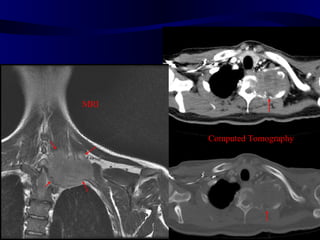

MRI Computed Tomography